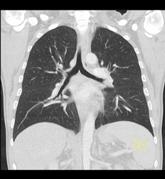

Die PET/CT ist in der Medizin derzeit die modernste zur Verfügung stehende bildgebende Untersuchung in der Diagnostik von Tumorleiden. Sie ermöglicht oft, sehr kleine Herde früher als mit anderen Verfahren wie Kernspintomographie (MRT) oder alleiniger Computertomographie (CT) zu entdecken. Ein besonderer Vorteil des Verfahrens besteht in der Kombination zweier bildgebender Verfahren, die sich perfekt ergänzen. Durch die CT Technik können Körperregionen und mittlerweile auch der gesamte Körper als vollständiger, lückenloser Datensatz erfasst werden. Dadurch entstehen Bilder in bis dahin ungeahnter Schnelligkeit und Qualität. Im PET werden im Gegensatz zum CT in erster Linie funktionelle Stoffwechselvorgänge im Körper dargestellt. Dazu wird Ihnen radioaktiv markierter Zucker (Glucose) in minimaler Menge in eine Vene injiziert. Die Verteilung im Körper wird mit einer speziellen Kamera (PET/CT-Scanner) gemessen, die Schnittbilder des Körpers gewinnt.

Die Glucose wird mit dem Radionuklid Fluor-18 markiert, das eine Halbwertzeit von 110 min hat. Das bedeutet, dass alle 2 Stunden die Radioaktivität um die Hälfte abnimmt. Zusätzlich wird innerhalb der ersten 2 Stunden ein Großteil der Radioaktivität über den Urin ausgeschieden. Insgesamt ergibt sich daraus eine durchschnittliche Strahlenbelastung von 6 mSv. Durch die PET wird also das Doppelte der natürlichen jährlichen Strahlenbelastung verursacht.

Zusammen mit der PET wird in der gleichen Untersuchung eine Computertomographie (CT) durchgeführt. Je nach Fragestellung und wenn schon Voraufnahmen vorhanden sind, wird das CT meist als Niedrig-Dosis CT ohne Röntgenkontrastmittel gefahren, d.h. mit niedriger Strahlenbelastung aber eingeschränkter Erkennbarkeit von anatomischen Details.

Ein Hybridgerät zwischen PET und CT in 64-Zeilen Technik wie am Klinikum Ludwigshafen kombiniert also in idealer Weise die detailgerechte hoch ortsaufgelöste Abbildung morphologischer und funktioneller Krankheitsaspekte insbesondere im Bereich der Onkologie.